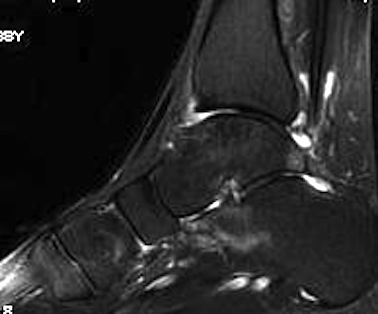

Subluxation of TNJ with advanced STJ OA

TNJ OA with posterior / medial / anterior facet OA of the subtalar joint

Union

Nonunion

Ankle joint arthritis

Ebalard et al Orthop Traumatol Surg Res 2014

- 72 hind and midfoot fusions with minimum 10 year follow up

- 73% tibiotalar arthritis